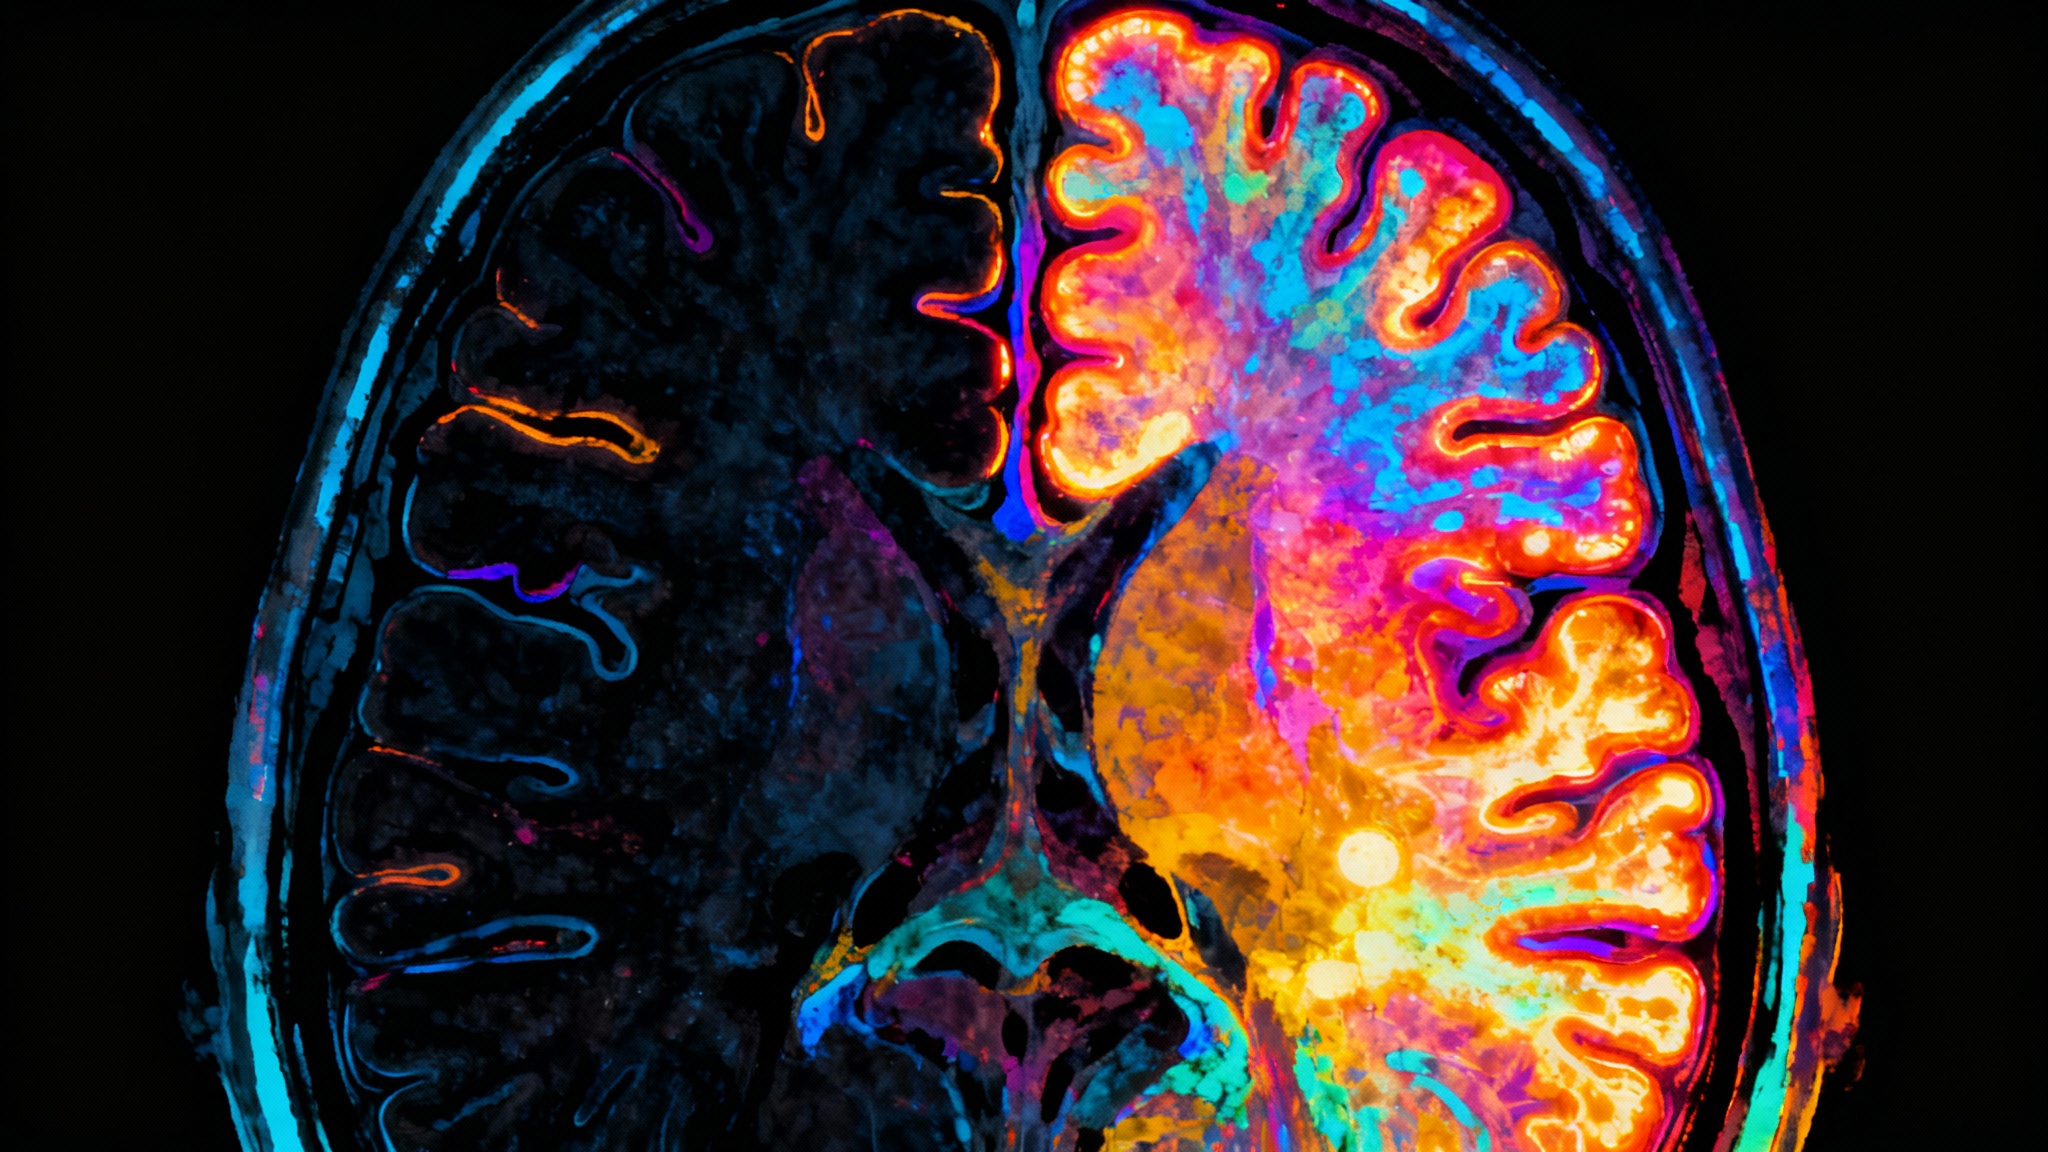

Le cerveau sous les projecteurs : que se passe-t-il vraiment ?

« Les rêves surviennent surtout en phase paradoxale, mais aussi en sommeil lent léger. En phase paradoxale, ils sont plus intenses, émotionnels et potentiellement bizarres », confirme Aurore Roland, doctorante à la Vrije Universiteit Brussel. C’est ce cocktail neurologique qui fait de nos nuits un terrain de jeu si imprévisible.